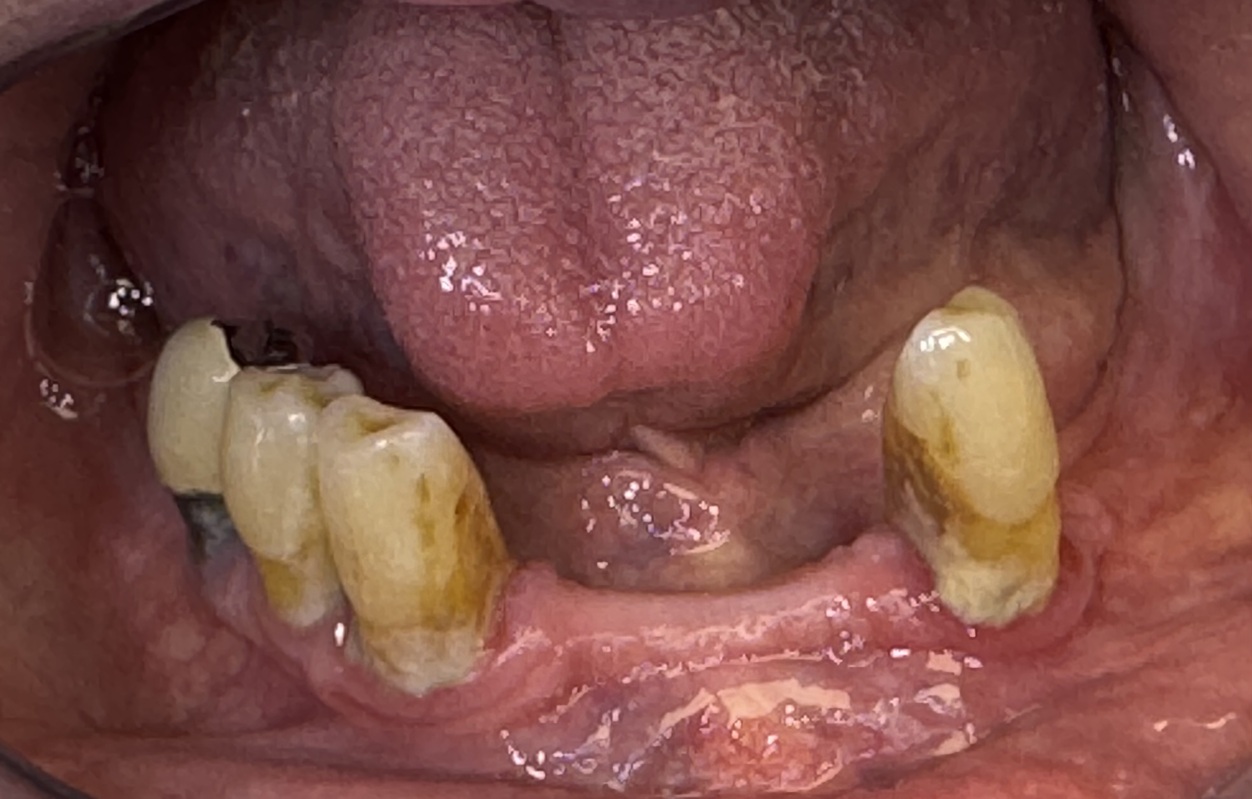

Patiente de 73 ans.

Ses dents du bas sont mobiles et douloureuses. Elles ne peuvent plus stabiliser l’ancienne prothèse du bas. La patiente vient nous voir dans l’attente d’une solution stable et esthétique.

La pose de 3 implants et les extractions sont réalisées dans la même séance; une prothèse transitoire stabilisée par 2 clips transitoires est mise en place le même jour.